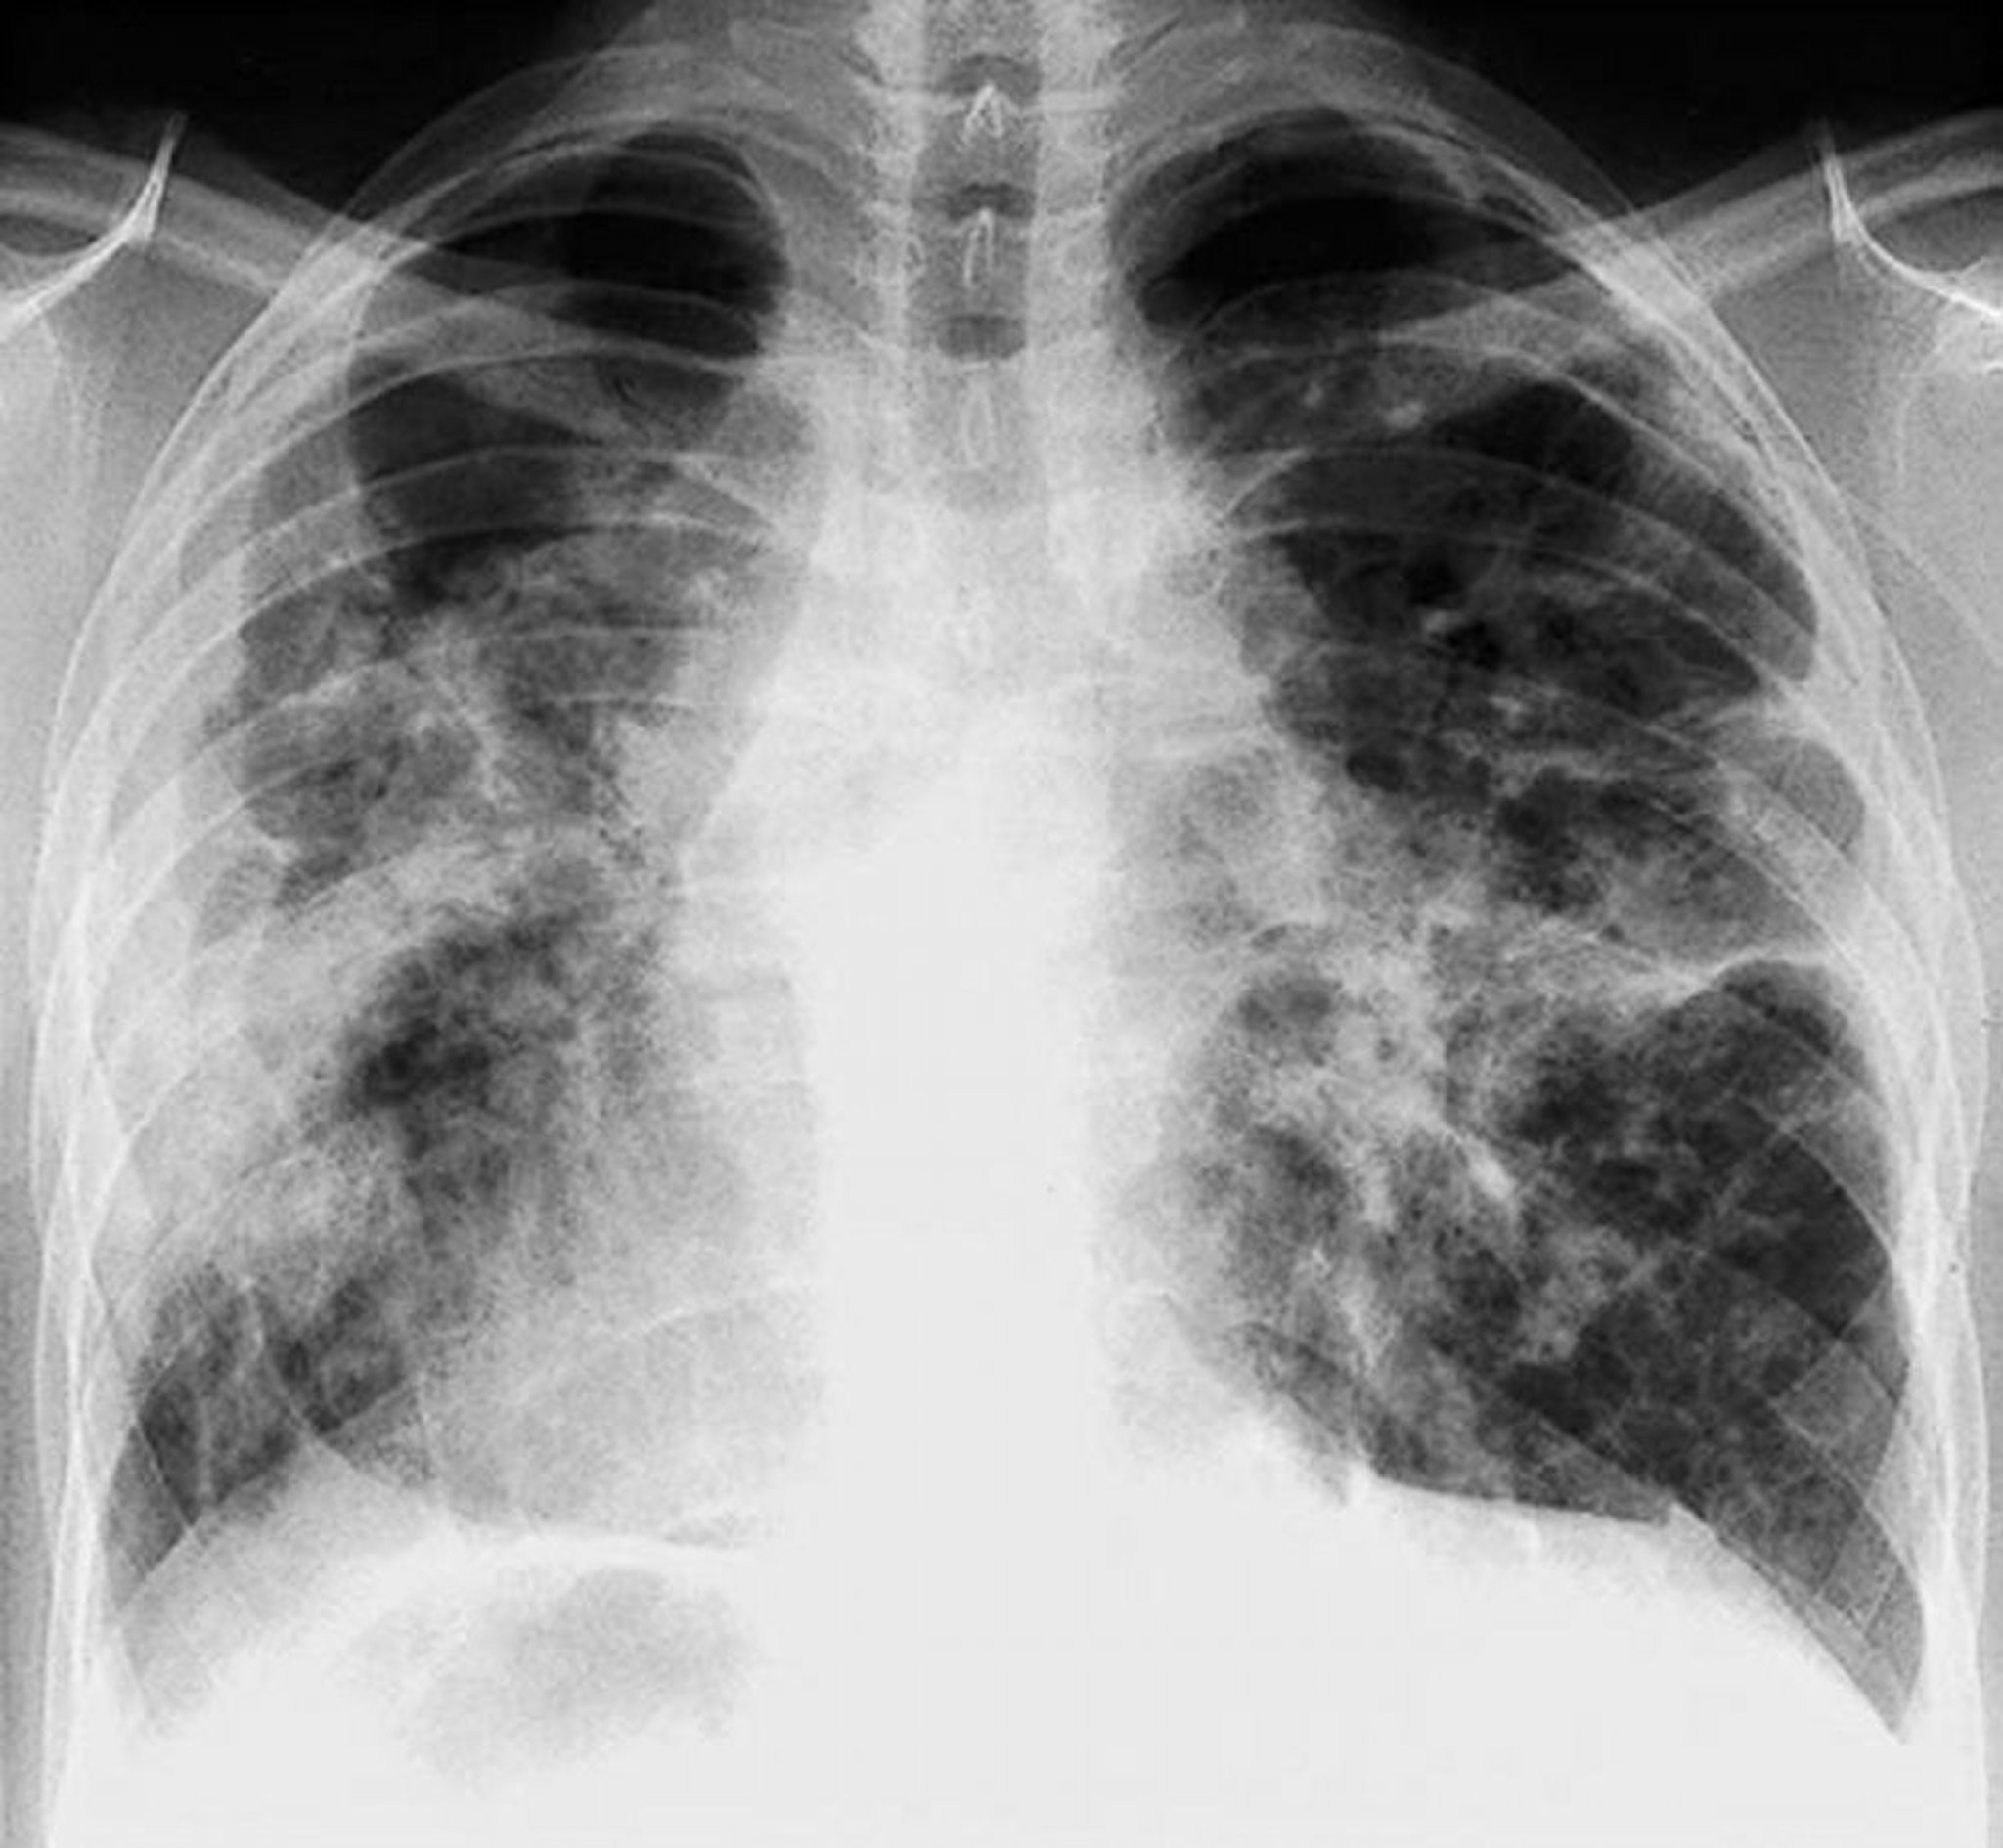

Sarkoidose (Stadium IV)

Schwere, diffuse Fibrose mit hilärer Adenopathie und zystischen Veränderungen der Oberlappen bei Sarkoidose im Stadium IV.